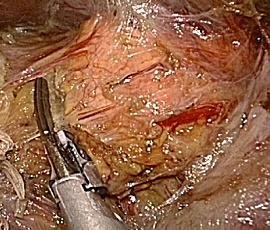

腹腔鏡下結腸・直腸切除術の実際

全身麻酔下で手術を行います。まず腹腔内(腹腔:お腹の壁と臓器との間の空間のことで

す)に炭酸ガスを入れて膨らませ、お臍からカメラ(腹腔鏡)を挿入します。この際、同

時に手、術操作に用いる器具(鉗子など)を挿入するために、5〜10mmの小さな穴を左

右に4ケ所開けます。そして腹腔鏡で撮ったお腹のなかの様子をモニターに映し出して、

大腸切除や周囲のリンパ節の切除を行います。開腹手術では見えにくかった細かい血管

や神経まで見えて繊細な手術操作が可能です。実際の腹腔鏡手術は、開腹手術と同じ全

身麻酔下で行います。

この手術は、専用の高性能カメラからの拡大した鮮明な画像を見ながら行うため従来の、

開腹手術では見えにくかった部位や細かい血管・神経まで見えて繊細な手術操作が可能

です。腹腔内で操作を終えたあとに最後に臍切開創を4−5cmに延長し病変をお腹の外

に取りだします。